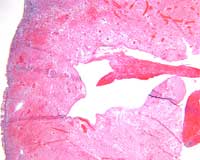

Microscopic evaluation of the interventricular septum and left ventricular anterior wall revealed subepicardial hemorrhage adjacent to regions of anemic infarction and patchy myocardial necrosis. The left ventricular cleft was surrounded by infarcted and necrotic myocardium with development of granulation tissue (Figures 9-10).

Figure 9

Figure 10